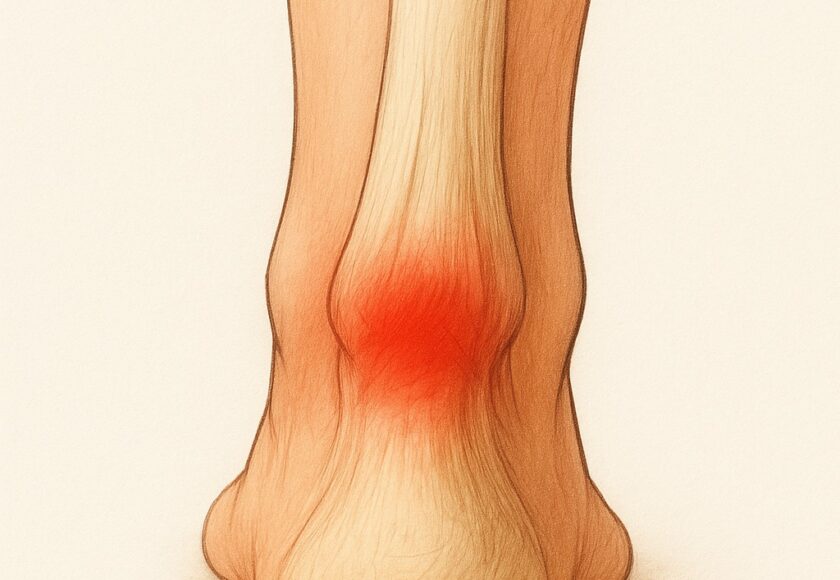

アキレス腱炎は、ふくらはぎからかかとの骨(踵骨)につながる太い腱に炎症が起こる障害です。

「かかとの後ろがズキズキ痛む」「走り始めに痛い」「朝の一歩目がつらい」などの症状が特徴です。

痛みが出やすい場所

アキレス腱の炎症は主に2つの部位に分けられます。

1.アキレス腱の中央部(腱の真ん中あたり)

・ふくらはぎと踵のちょうど間、腱の途中に炎症が起きるタイプ

・ランニングやジャンプの繰り返しで起こりやすい

・押すと硬くしこりのように感じることもある

2.アキレス腱付着部(かかとの骨に近い部分)

・踵の少し上、腱が骨にくっつく部分に炎症が出るタイプ

・シューズのかかとが当たって痛むことも多い

・骨の出っ張り(骨化や隆起)が伴う場合もある